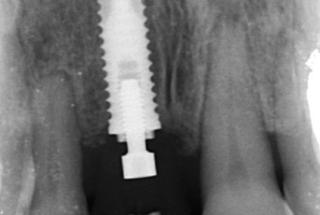

Clinical cases

MPI closely monitors clinical cases in the market to ensure their correct functioning and successful outcome.